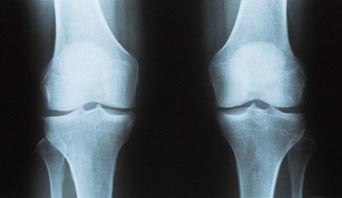

Last updated: 17th February, 2021  Osteoporosis is a health problem that causes the bones to become brittle and weak. So feeble that even a slight movement like bending over can cause a fracture. Furthermore, most of these osteoporosis-related fractures occur in the wrist, hip, or spine. Both men and women can become susceptible to osteoporosis. However, […]

Last updated: 7th April, 2020  Osteoporosis is one of the common bone problems, which causes 8.9 million fractures every year worldwide. It is characterized by thinning and weakening of the bone to a point that they become prone to fracture and breakage. According to a research, published in the Journal Geriatric Nursing, Osteoporosis is a condition that can take even a lifetime […]